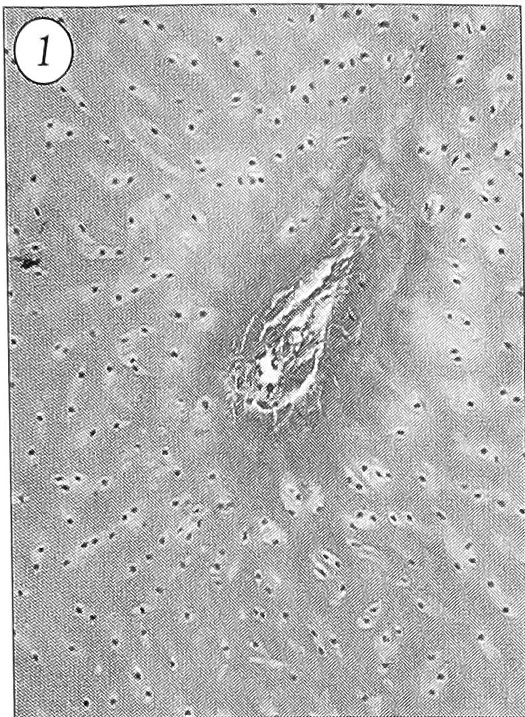

При гистологическом исследовании обнаружено, что у 6 из 16 больных тяж представлял собой типичный гиалиновый хрящ (рис. 1). Макроскопически он характеризовался как фиброзно-хрящевой. Хондроциты были многочисленными, мелкими, имели веретенообразную форму, равномерно распределялись в матриксе, умеренно богатом кислыми гликозаминогликанами. По периферии поперечного среза тяжа они располагались преимущественно радиально, в остальных отделах — беспорядочно. Во всех образцах можно было видеть многочисленные изогенные группы, содержащие 2-4, реже 8 хондроцитов (рис. 2), что свидетельствовало об интерстициальном росте. Все 6 хрящевых образований были покрыты толстой (до 300-400 мкм) надхрящницей без клеточного слоя. При повторной операции у одного больного структура тяжа оказалась аналогичной той, которая была обнаружена при первой операции. У 2 больных при иссечении хрящевых тяжей с прилежащей костью выявлен рост кости энхондральным путем. Слой костеобразования был четко выражен, величина его достигала 600 мкм (рис. 3).

Рис. 1. Гиалиновый хрящ тяжа с каналом кровеносного сосуда. Ув. 7,6x20.

Здесь и на рис. 2~5 окраска по Ван-Гизону.

Рис. 2. Изогенные группы хондроцитов. Ув. 15,4x20.